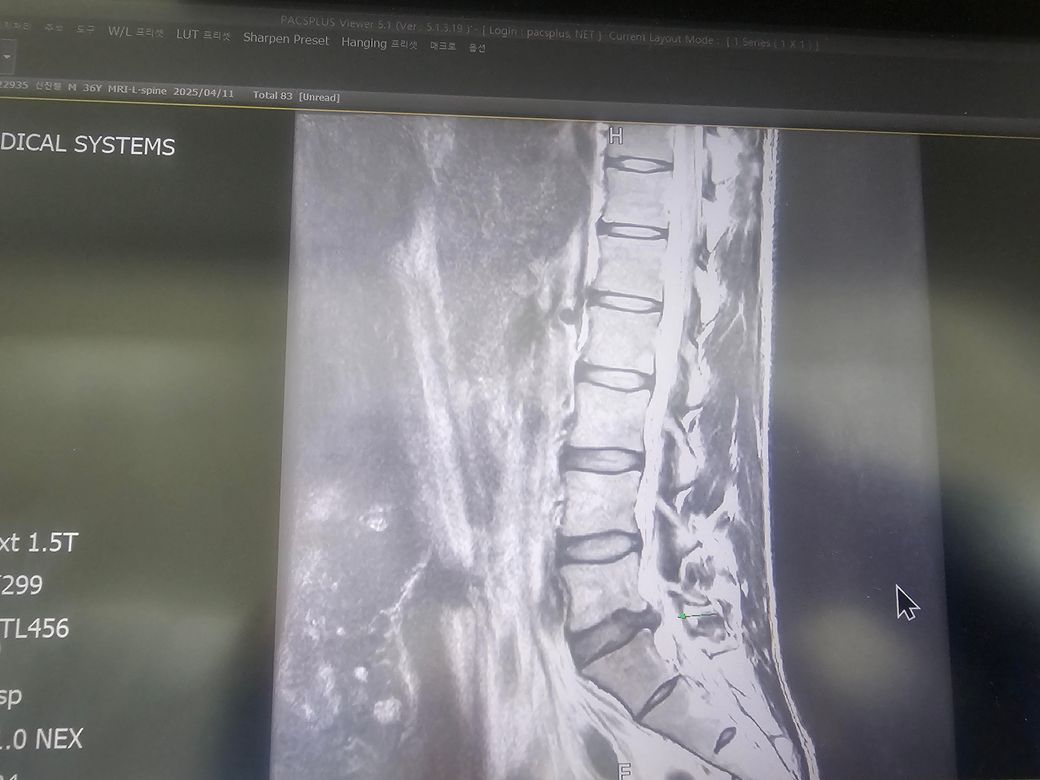

힘들어서 잠깐 쭈그렸다가 일어서는 중 극심한통증이 느껴져 그대로 바닦에 누워 동료분들의 도움으로 구급차를 타고 병원으로 이동했습니다. mri 촬영결과 심한건아니지만 디스크가 조금 나왔고 신경을 건드려 아픈것으로 보이며, 수술까진 아니더라도 주사치료와 물리치료를 해야한다고 안내받고 거동이 안되어 입원을 하게되었습니다.

참고용으로 mri 첨부합니다. 아직 입원중으로 병명코드등은 확인이 어렵습니다. 많은 자문부탁드립니다.